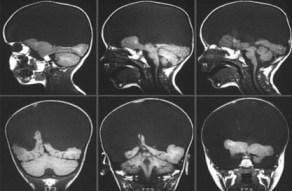

(انعدام الدماغ)

هو عدم وجود جزء كبير من الدماغ أو الجمجمة أو فروة الرأس (الجلد المغطي للجمجمة) التي تحدث أثناء التطور الجنيني. وهو مرض رأسي ناتج عن عيب في تكوين الأنبوب العصبي الذي تحدث عند عدم إغلاق النهاية الرأسية للأنبوب العصبي. و انغلاق المسام الرأسي للأنبوب العصبي يكون عادة في اليوم 23-26 من الحمل تقريبا ، فإذا لم ينغلق فإن ذلك يتسبب بحالة انعدام الدماغ. ومع أن المصطلح الإغريقي Anencephaly يعني عدم وجود ما بداخل الرأس نهائيا، أي أن الدماغ غير موجود نهائيا، إلا أن الأجنة المصابين بهذا العيب يفتقدون فقط الدماغ الانتهائي telencephalon .الجزء الأكبر من الدماغ والذي يتكوِّن عموماً من نصفي الكرة المخية ( cerebral hemispheres ) بما في ذلك القشرة المخية الحديثة ( neocortex ) المسؤولة عن الإدراك.أما الجزء الباقي فيكون مغطى بغشاء رقيق، وبالنسبة للجلد والعظم والسحايا فتكون كلها مفقودة.وفي ظل ما سبق واستثناءات قليلة فالمواليد الجدد بهذا المرض لا يعيشون لمدة ساعات أو أيام بعد ولادتهم .